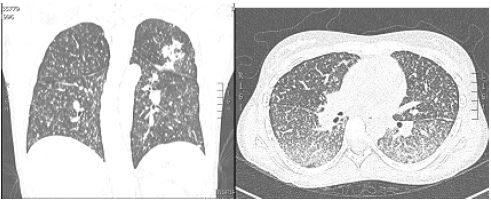

El caso corresponde a una mujer de 20 años de edad, quien presentó un cuadro clínico de 6 meses de evolución de diarreas con moco, sangre, dolor abdominal y pérdida de peso (3-4 kg). La colonoscopia realizada evidenció afectación inflamatoria ileocolónica, por lo que se le tomaron biopsias escalonadas, donde se reportó colitis crónica con aumento significativo de los eosinófilos (60 × CAP). Se sospechó inicialmente una colitis eosinofílica y, por ello, se le dio tratamiento con deflazacort (6 mg cada 12 horas) y mesalazina oral (3 g/día) durante casi 2 meses. A pesar de este tratamiento, persistía sintomática; entonces, una nueva colonoscopia evidenció pancolitis ulcerada con mayor compromiso del lado derecho ( figura 3), con cambios inflamatorios y úlceras en ileon distal.

Las biopsias revelaron una arquitectura remplazada por el proceso inflamatorio, con ulceración completa y focos de infiltrado inflamatorio polimorfonuclear, neutrófilos y linfoplasmocitario (áreas de cronicidad), con granulomas no caseificantes (Ziehl-Neelsen, Ziehl-Neelsen modificado, PAS y plata metenamina negativos para bacilos acido alcohol resistente [BAAR] y hongos) e inmunohistoquímica de citomegalovirus negativos. Se consideró un diagnóstico presuntivo de EC con afectación predominante ileocolónica. Se le dejó tratamiento con hidrocortisona intravenosa (50 mg cada 6 h), mesalazina oral (1 g cada 8 h) y enemas de mesalazina (4 g/día).